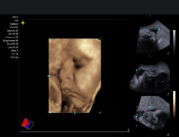

fourSight 4D technology 四维成像功能

‒ 实时三维成像

‒ 适用于腔内容积探头 8VC3 和 腹部容积探头 9VE3

‒ 提供多种高级四维成像功能:

多层断层成像、厚层断层成像和曲线任意多平面成像模式